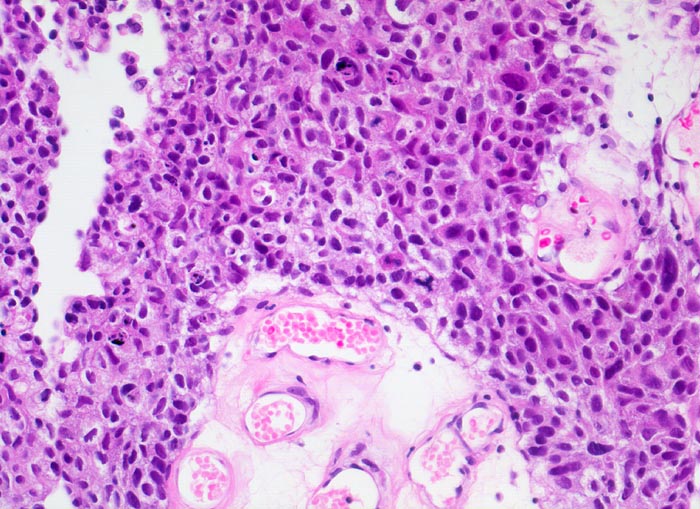

PathoPic – image database / PathoPic ID 3996 - Wenig differenziertes papilläres Urothelkarzinom G3

Wenig differenziertes papilläres Urothelkarzinom G3

Ödematöses Papillenstroma. Urothel verbreitert, mit ausgeprägter Polymorphie und Verlust der Polarität. Zahlreiche Apoptosen und eine atypische Mitose.

Stromainvasion an anderer Stelle und assoziiertes Carcinoma in situ.

Papillärer Harnblasentumor. Makrohämaturie.